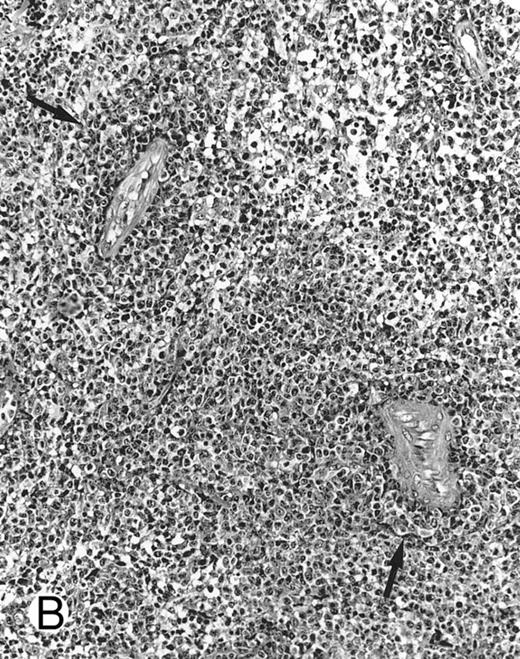

Nasal-type NK/T-cell lymphoma presenting as nodular skin lesion (case no. 28). (A) The skin shows focal necrosis of the epidermis and ulceration (arrow). (B) The lymphoid infiltrate in the dermis shows angiocentricity, as evidenced of the higher density of cells in the expanded walls of the blood vessels (arrows).

Histologically, the lymphomatous infiltrate was diffuse or patchy, with angiocentric and angiodestructive growth being observed in 30 cases (88.2%) (Figs 1 and 2). The cytologic composition was variable from case to case, including predominance of small cells, medium-sized cells, or large cells, or a mixture of these cell types (Fig 2 and 3). The tumor cell nuclei frequently showed irregular foldings and granular chromatin (Fig 2B). The larger cells possessed distinct nucleoli. The cytoplasm was moderate in amount and often pale. Karyorrhexis was usually prominent. Zonal tumor cell death, focal or confluent, was evident in 27 cases. In the 14 cases for which Giemsa-stained touch preparations were available, azurophilic granules could be identified in at least some of the neoplastic cells.